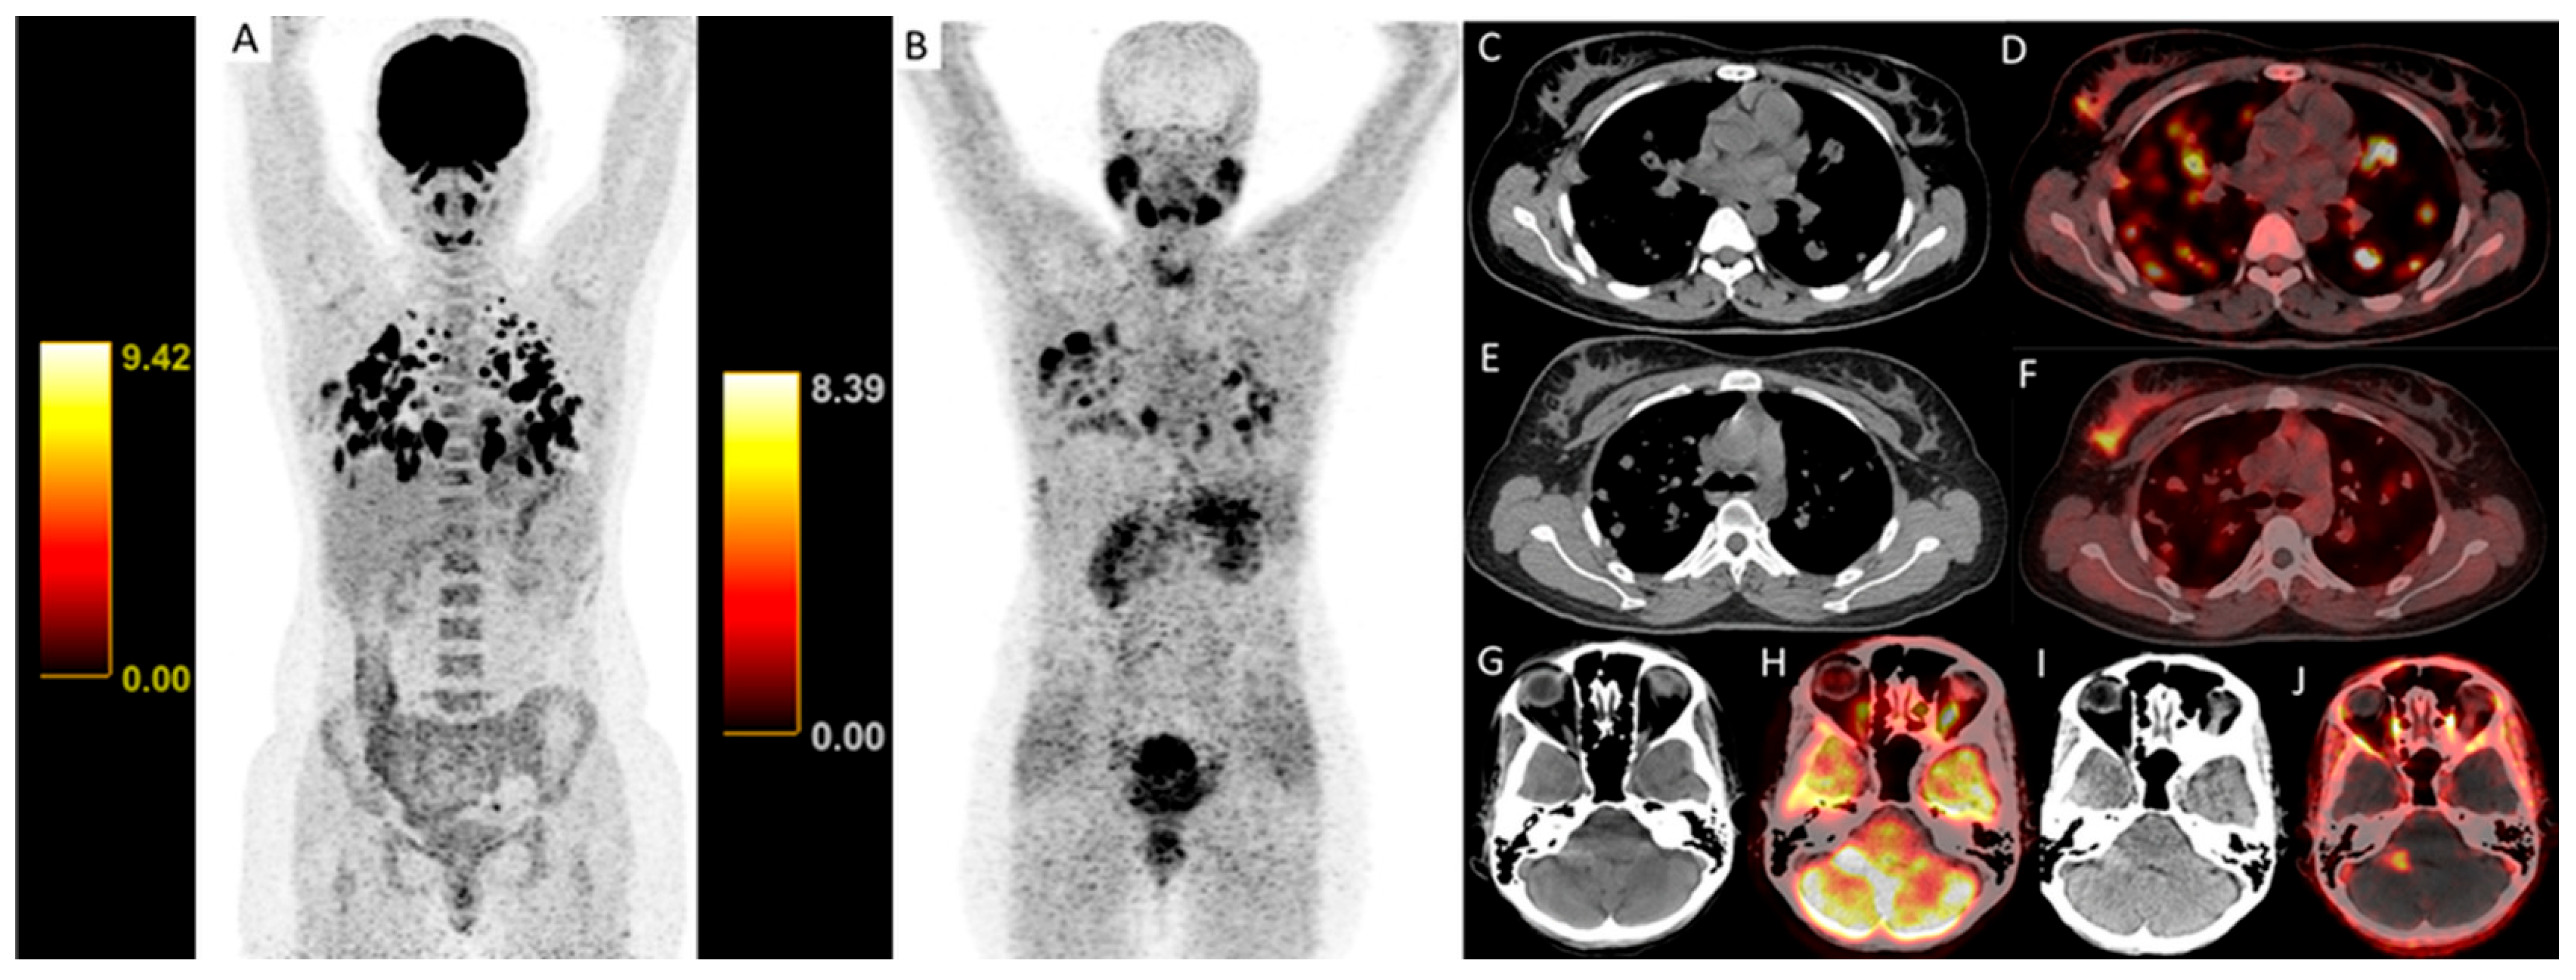

| Brain background SUVmax | 0.73 ± 0.26 | 7.35 (6.53–10.48) | <0.001 ** |

| TBR (brain metastases) | 3.62 (2.19–5.09) | 0.00 (0.00–0.00) | <0.001 ** |